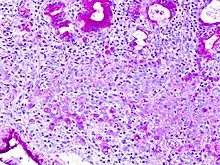

En histología, una célula en anillo de sello es aquella célula con una vacuola grande. El tipo maligno se observa predominantemente en carcinomas.

El nombre de la célula proviene su aspecto; las células en anillo de sello aparentan ser anillos de sello . Contienen una gran cantidad de mucina, la cual empuja al núcleo hacia la periferia de célula. El contenido de mucina en las células en anillo de sello imita la apariencia de un agujero para el dedo y el núcleo imita aspecto de la cara del anillo en perfil.